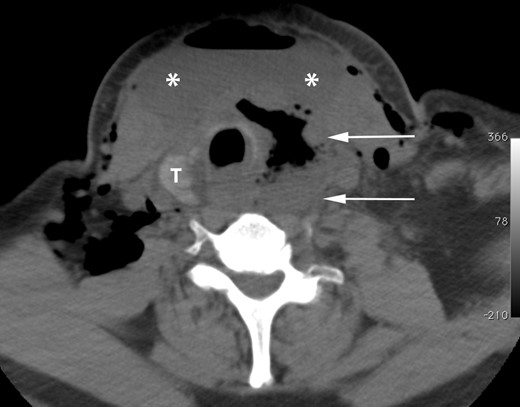

On the third postoperative day, however, the patient returned to the surgeon's office with complaints of neck pain and swelling. A CT scan of the neck performed at that time revealed a 7.7 × 3.7 cm fluid collection in the left neck (Fig. 1). The patient was taken emergently to the operating room, where upon opening the incision a large amount of purulent fluid was evacuated. There was a thick, yellowish exudate adherent to the involved surfaces, and the strap muscles were noted to be thickened, stiff and friable. Inspection of the esophagus revealed no obvious injury, but surrounding tissues were noted to be discolored and inflamed, making visualization of the esophagus difficult. The recurrent laryngeal nerve, which had been identified during the initial operation, was not seen.

Axial CT image of the neck without oral or intravenous contrast demonstrates an air fluid collection in the left thyroid lobectomy bed (white arrows). Subcutaneous emphysema and a large anterior neck air fluid collection (asterisks) are also present. T, residual right lobe of the thyroid.